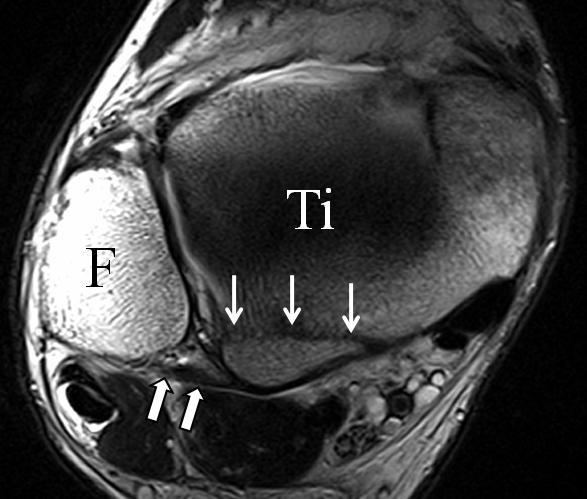

b. T2 fs axial. Infraktion des hinteren Volkmann‘schen Dreiecks (schmale, weiße Pfeile). Hier inserierende, intakte, hintere Syndesmose (breite, weiße Pfeile).

Abbildung 18b

Das Ligamentum tibiofibulare posterius (hintere Syndesmose) verläuft flacher und geht nach kranial in das Ligamentum tibiofibulare interosseus und nach kaudal in das Ligamentum intermalleolare posterius über. Letzteres bildet ein artikuläres Labrum zwischen Trochlea und Talus 9.

Da also die hintere Syndesmose an der posterioren Tibia inseriert, entspricht eine Fraktur oder Infraktion des hinteren Volkmann`schen Dreiecks funktionell einem knöchernen Ausriss des Ligamentum tibiofibulare posterius (Abb. 18 a und b). Aufgrund der Koinzidenz von Syndesmosenläsionen mit Innenbandverletzungen ist bei der Beurteilung gesondert auf solche zu achten.